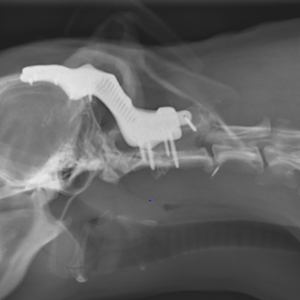

Frakturen im Bereich der Wirbelsäule bedürfen meist ebenso einer chirurgischen Versorgung, da es sonst zu einer Schädigung des Rückenmarks mit bleibenden neurologischen Ausfällen kommen kann. Dies wird in der Regel durch spezielle Schrauben, Knochenzement und / oder Platten bewerkstelligt.

Auch andere Wirbelsäulenerkrankungen, die das Rückenmark durch Instabilität oder Kompression beeinflussen, werden je nach Indikationsstellung neurochirurgisch entsprechend versorgt (z.B. Degenerative lumbosakrale Stenose, Zervikale Spondylomyelopathie, Atlantoaxiale Instabilität und andere Mißildungen). Bei Bedarf kommen auch individualisierte Implantate zum Einsatz.

Individualisiertes Titanimplantat bei Instabilität durch multiple Missbildungen, © Kleintierklinik der LMU